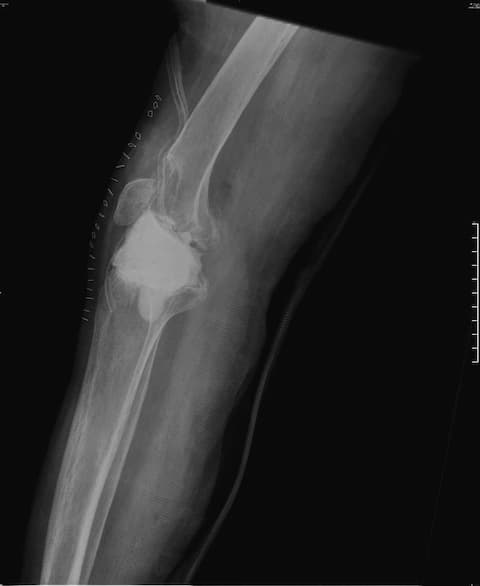

Тохиолдол танилцуулга 7.

Өвчтөн: П.Ц 60 настай, эмэгтэй 2019.1.4

Үе дайрсан ясны анхдагч хавдар, ясны дутмагшлын үед хийгдэх мэс засалimg31Үе дайрсан ясны анхдагч хавдар, ясны дутмагшлын үед хийгдэх мэс засалimg32

Зураг 1. Сэргээн засах мэс заслын өмнөх рентген зураг. Эгц урд, хажуугаас авсан байдал.